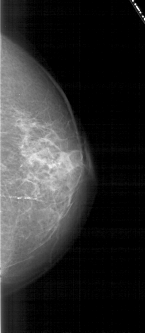

A_1820_1.LEFT_CC

LEFT_CC LINES 5086 PIXELS_PER_LINE 2536 BITS_PER_PIXEL 12 RESOLUTION 43.5 OVERLAY

FILE: A_1820_1.LEFT_CC.OVERLAY

TOTAL_ABNORMALITIES 1

ABNORMALITY 1

LESION_TYPE MASS SHAPE OVAL MARGINS ILL_DEFINED

ASSESSMENT 4

SUBTLETY 4

PATHOLOGY MALIGNANT

TOTAL_OUTLINES 1

BOUNDARY